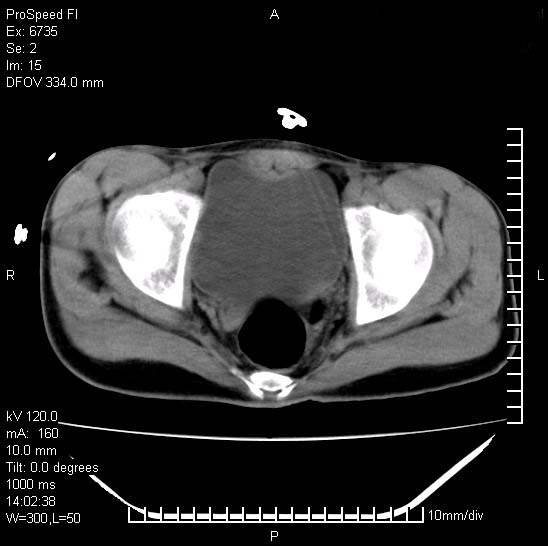

患者自诉胯部疼痛两年余,在当地服用中药,半月前至本院考虑骶髂关节结核,给予抗痨治疗。现发展至右下肢疼痛明显,活动受限,以膝关节处明显,拍膝关节平片无明显异常。

两侧骶骼关节改变,考虑强直性脊炎

左侧骶髂关节面限局性骨破坏,边缘硬化关节腔见钙化物;不出外tb

右侧骶髂关节也有类似改变,只是较左侧轻,首先考虑强直性脊柱炎,不除外结核,建议作hla-b27检查。

典型强脊炎改变,髋关节亦有累及

符合强直性脊柱炎表现。